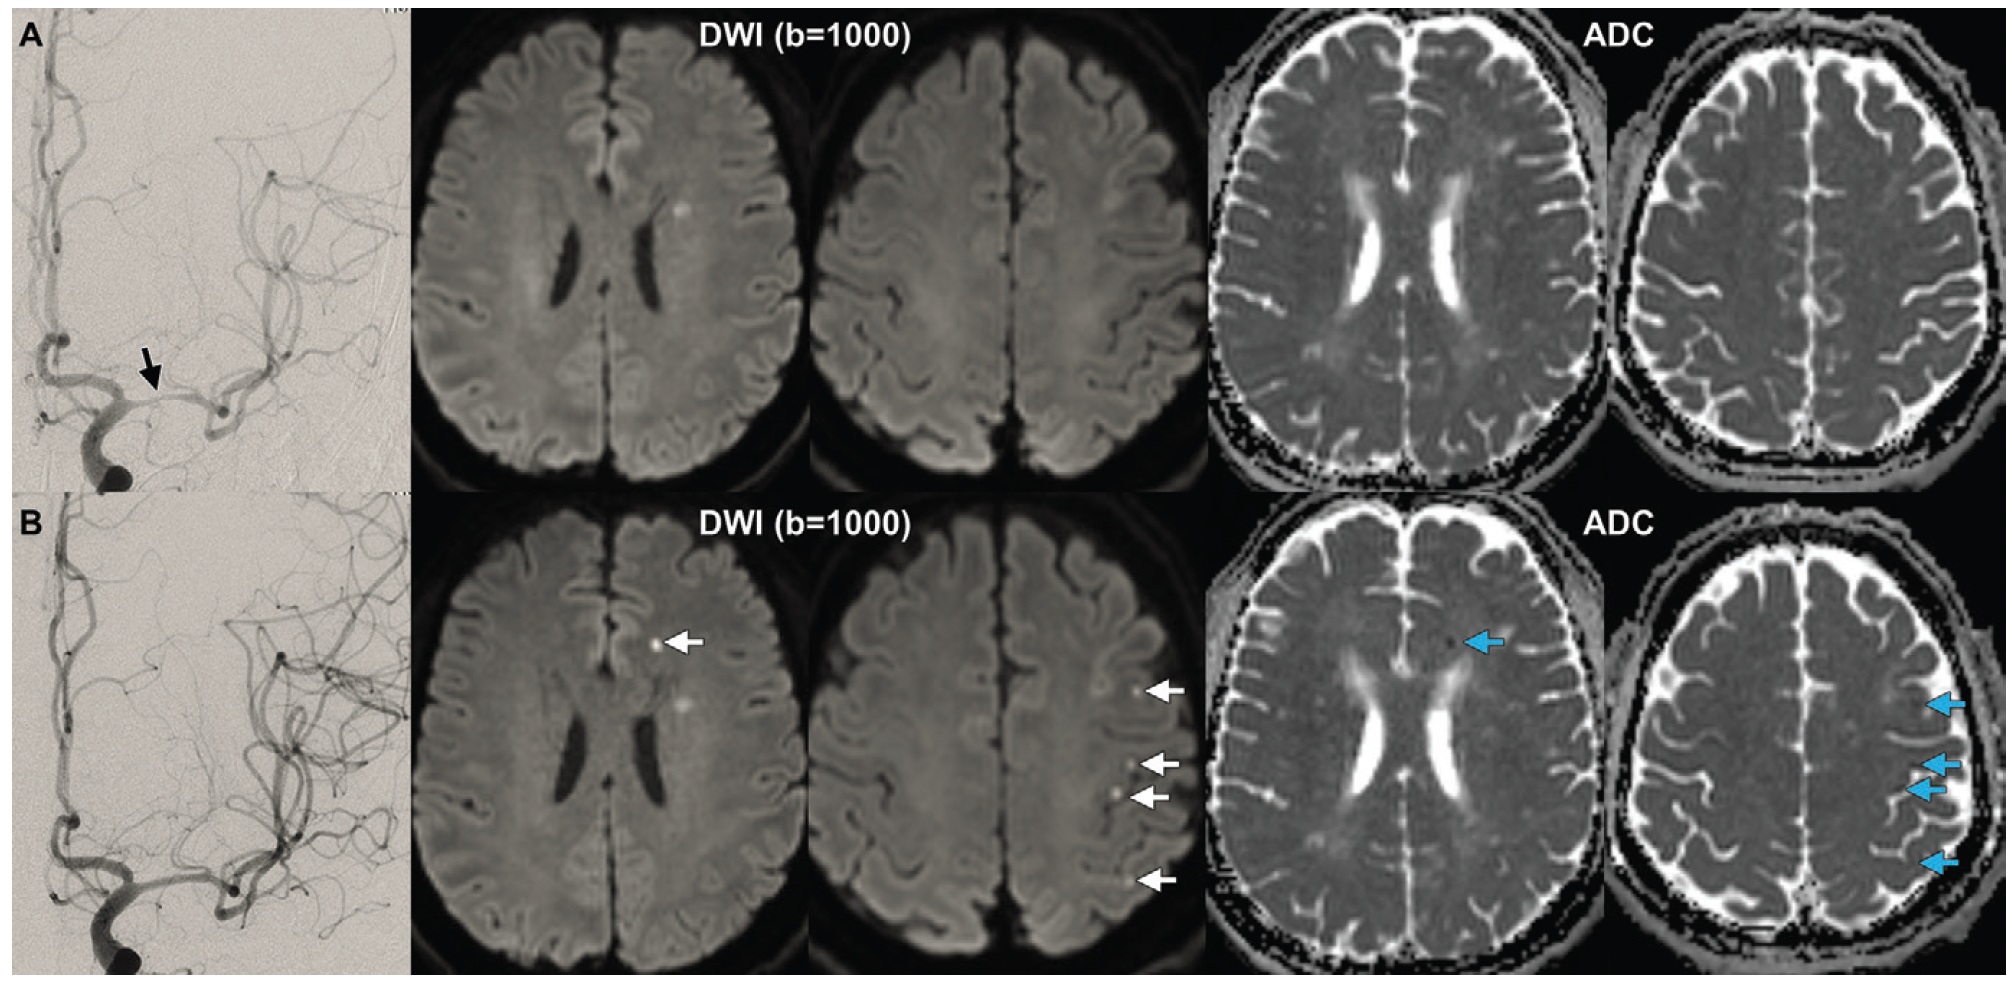

In the study of 119 patients who had endovascular treatment for intracranial atherosclerotic stenosis, multivariable analysis revealed that post-op ischemic brain lesions on diffusion-weighted magnetic resonance imaging (MRI) were 3.6 times more likely to occur in patients who smoke cigarettes and 2.9 times more likely in patients who had multiple operative attempts.